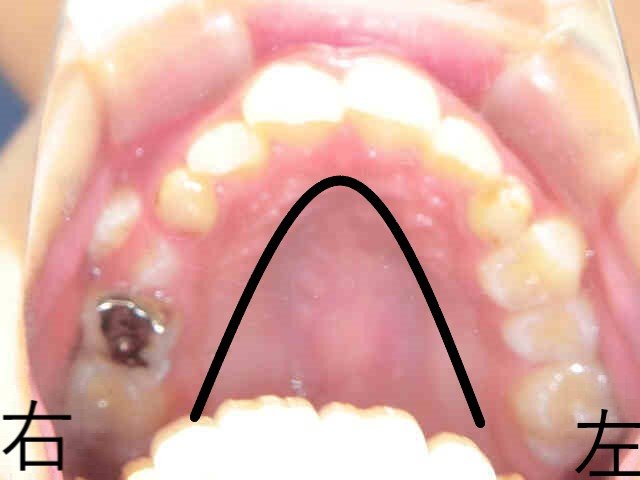

左上の写真は、治療開始前の上顎を下から撮影したもので、歯列が左右に狭くV字型になっていることがわかります。

右上は下顎を上から見た写真で、上顎の狭窄により、下顎の奥歯が内側に倒れ、前歯部には叢生(歯の重なり)が見られます。